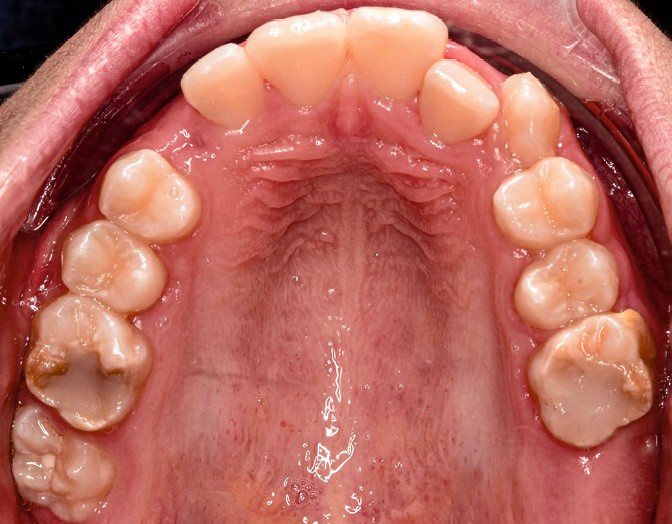

Fares, 13 ans, est adressé par son dentiste pour un bilan orthodontique dans le cadre d’une Hypominéralisation Molaire-Incisive (MIH). L’enfant est en bonne santé générale.

L’examen clinique montre une MIH sévère sur 16, 26, 36 et 46, et modérée sur 11 et 21.

Sur le plan alvéolo-dentaire (fig. 1b) :